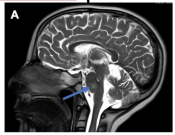

Image"Diffuse midline glioma with extra central nervous system metastases in the pediatric, adolescent, and young adult population," was published in Child's Nervous System on October 7th by Dr. Jeffrey P. Greenfield.